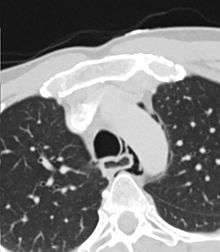

Axial CT image through the upper chest showing extraluminal air(pneumediastinum) surrounding the trachea and esophagus

The diagnosis of Boerhaave's syndrome is suggested on the plain chest radiography and confirmed by chest CT scan. The initial plain chest radiograph is almost always abnormal in patients with Boerhaave's syndrome and usually reveals mediastinal or free peritoneal air as the initial radiologic manifestation. With cervical esophageal perforations, plain films of the neck show air in the soft tissues of the prevertebral space.

Hours to days later, pleural effusion(s) with or without pneumothorax, widened mediastinum, and subcutaneous emphysema are typically seen. CT scan may show esophageal wall edema and thickening, extraesophageal air, periesophageal fluid with or without gas bubbles, mediastinal widening, and air and fluid in the pleural spaces, retroperitoneum or lesser sac.